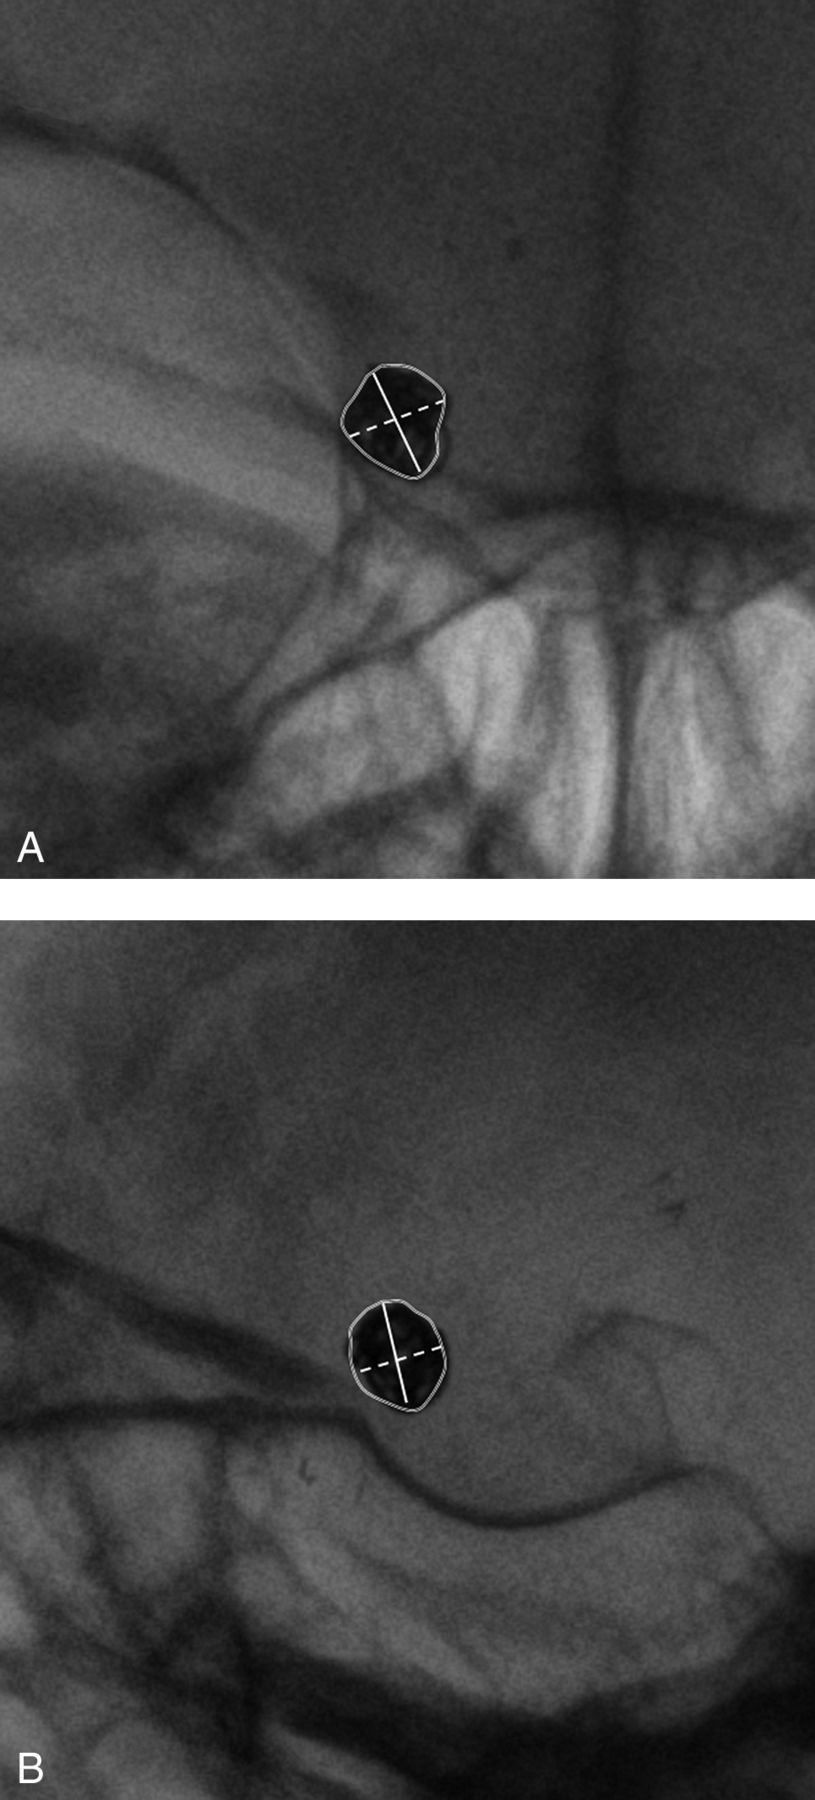

Two independent radiologists (W.S.J., S.J.A.) estimated the largest diameter of the coil mass (LAP) and the diameter perpendicular to the LAP (PAP) on the skull AP view.18 On the skull lateral view, the largest diameter (LLat) and the diameter perpendicular to the LLat (PLat) were also measured in the same way. In measuring the area of the coil mass, a region of interest was drawn manually along the border of the coil mass on the skull plain films, and the areas on skull AP (AAP) and lateral views (ALat) were automatically calculated from the same image workstation (Figure). Quantitative change in each parameter was defined as the absolute difference of each parameter measured in the paired skull plain films.

Quantitative measurement of a coiled aneurysm on the right distal ICA. The largest diameter, perpendicular diameter, and area of the coil mass are measured on skull AP (A) and lateral (B) views. The solid line indicates the largest diameter, and the dashed line is the perpendicular diameter. The area within the solid circle was automatically calculated.